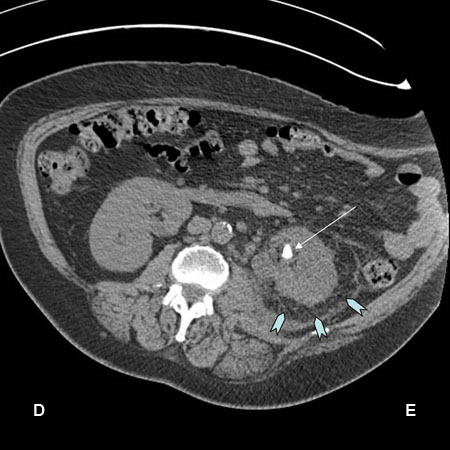

[Figure caption and citation for the preceding image starts]: Tomografia computadorizada (TC) mostrando nefrolitíase esquerda (seta branca) com stranding perinéfrico ao redor do rim esquerdo (setas azuis) e pielonefriteDa coleção pessoal do Dr. Kasra Saeb-Parsy [Citation ends].